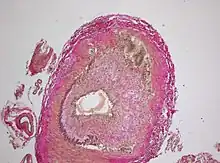

The gold standard for diagnosing temporal arteritis is biopsy, which involves removing a small part of the vessel under local anesthesia and examining it microscopically for giant cells infiltrating the tissue.[19] However, a negative result does not definitively rule out the diagnosis; since the blood vessels are involved in a patchy pattern, there may be unaffected areas on the vessel and the biopsy might have been taken from these parts. Unilateral biopsy of a 1.5–3 cm length is 85-90% sensitive (1 cm is the minimum).[20] A characterised as intimal hyperplasia and medial granulomatous inflammation with elastic lamina fragmentation with a CD 4+ predominant T cell infiltrate, currently biopsy is only considered confirmatory for the clinical diagnosis, or one of the diagnostic criteria.

Histological features of temporal arteritis -

Intermediate magnification micrograph showing giant cell arteritis in a temporal artery biopsy. The arterial lumen is seen on the left. A giant cell is seen on the right at the interface between the thickened intima and media. H&E stain -

Histopathology of giant cell vasculitis in a cerebral artery. Elastica-stain.